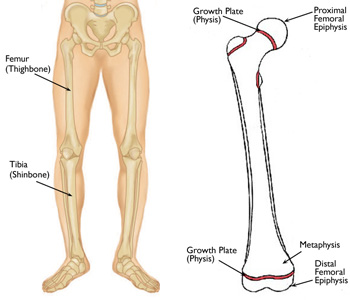

In most cases, the bones affected by a leg length discrepancy are the femur (thighbone) and tibia (shinbone).

Like the other long bones in the body, the femur and tibia do not grow from the center outward. Instead, growth occurs around the growth plates. Growth plates are areas of cartilage located between the widened part of the shaft of the bone (the metaphysis) and the end of the bone (the epiphysis).

If illness or injury damages the growth plate, the bone may grow at a faster or slower rate than the bone on the opposite side.

(Left) A discrepancy most often involves the femur or tibia. (Right) The location of the growth plates at the ends of the femur.